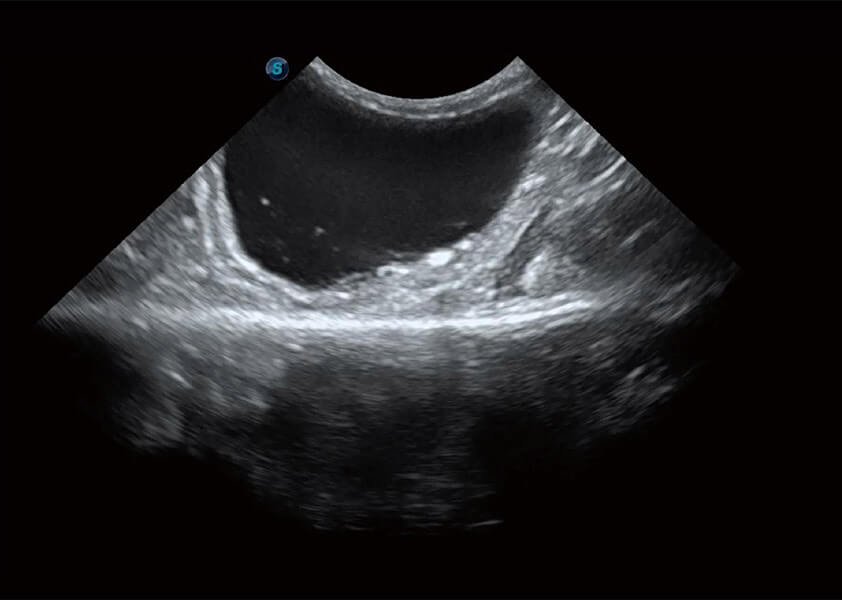

(犬)胆囊泥沙